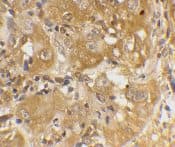

Rabbit Polyclonal Bim antibody. Suitable for WB, IHC-P, ICC/IF and reacts with Rat, Human samples. Cited in 23 publications. Immunogen corresponding to Synthetic Peptide within Human BCL2L11 aa 1-50.

Applications ICC/IF, IHC-P, WB